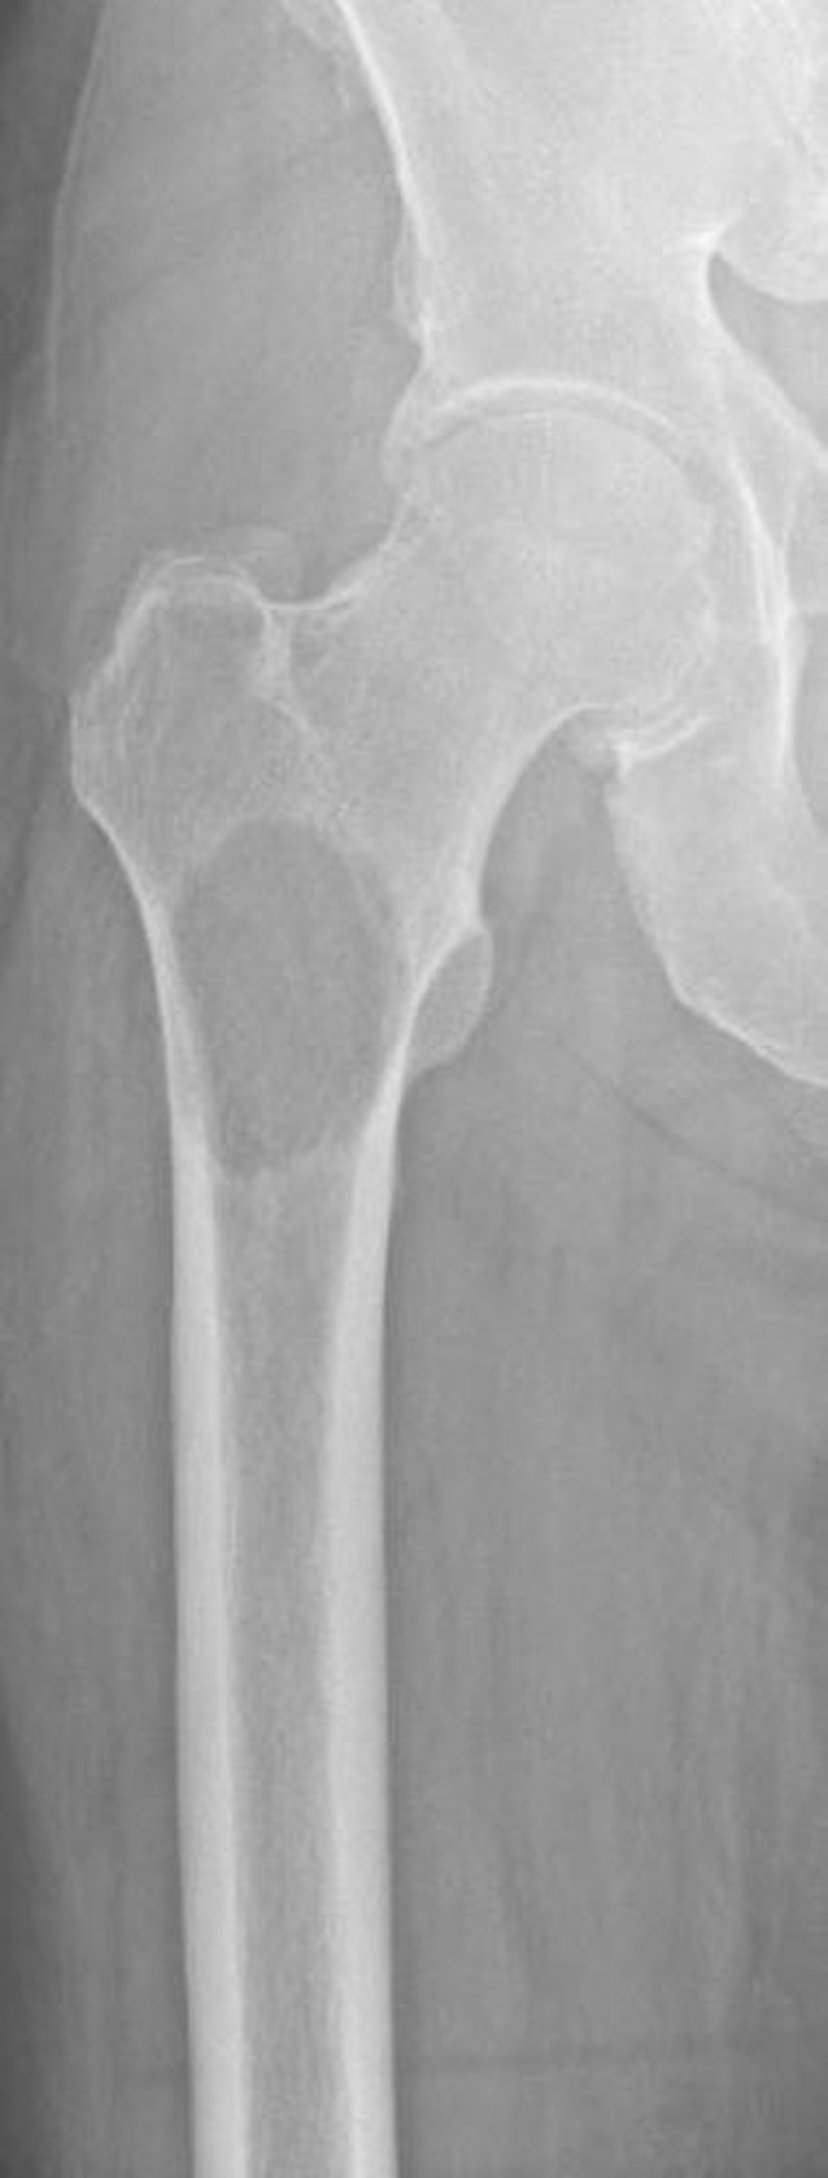

Métastases lytiques du fémur proximal

Cette image montre une destruction osseuse due à une métastase secondaire à un carcinome à cellules rénales au niveau du fémur proximal. L'emplacement et l'importance de la destruction osseuse rendent le risque de fracture extrêmement élevé (fracture imminente).

Image courtoisie de Michael J. Joyce, MD, and David M. Joyce, MD.